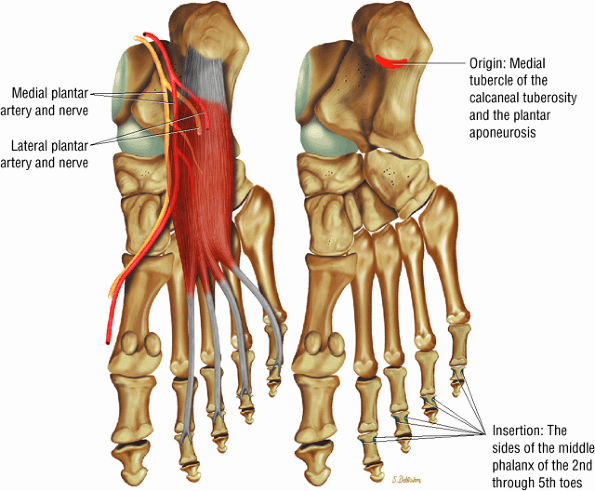

The muscles of the foot are the extensor digitorum brevis (Fig. 5.14), the abductor hallucis (Fig. 5.15), the flexor digitorum brevis (Fig. 5.16), the abductor digiti minimi (Fig. 5.17), the quadratus plantae (Fig. 5.18), the lumbricals (Fig. 5.19), the flexor hallucis brevis (Fig. 5.20), the adductor hallucis (Fig. 5.21), the flexor digiti minimi brevis (Fig. 5.22), the dorsal interossei (Fig. 5.23), and the plantar interossei muscles (Fig. 5.24).

FIGURE 5.16 ● FLEXOR DIGITORUM BREVIS The flexor digitorum brevis (FDB) divides into two slips to allow the passage of the flexor digitorum longus tendon. The FDB flexes the middle phalanges (PIP joints) and is a weak plantarflexor of the MP joint (for the lateral four toes).